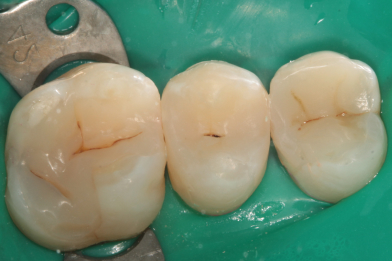

Жалобы на застревание пищи между зубами 26,25, реакция на сладкое и

Колиш Максим Петрович

холодное.

При осмотре обнаружен контактный кариес на зубах 26,25.

Лечений в один визит , восстановление функциональности композитной

реставрацией. -